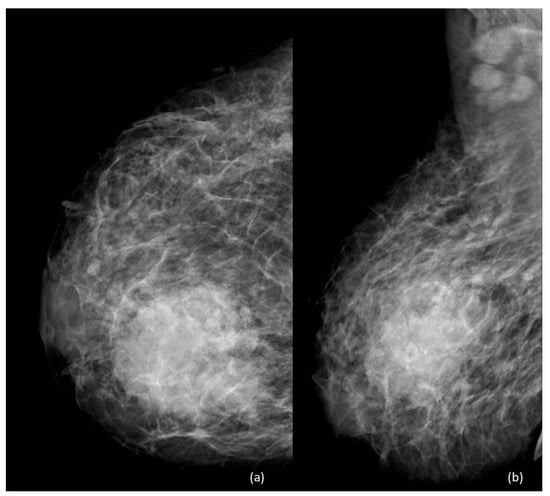

4. Imaging